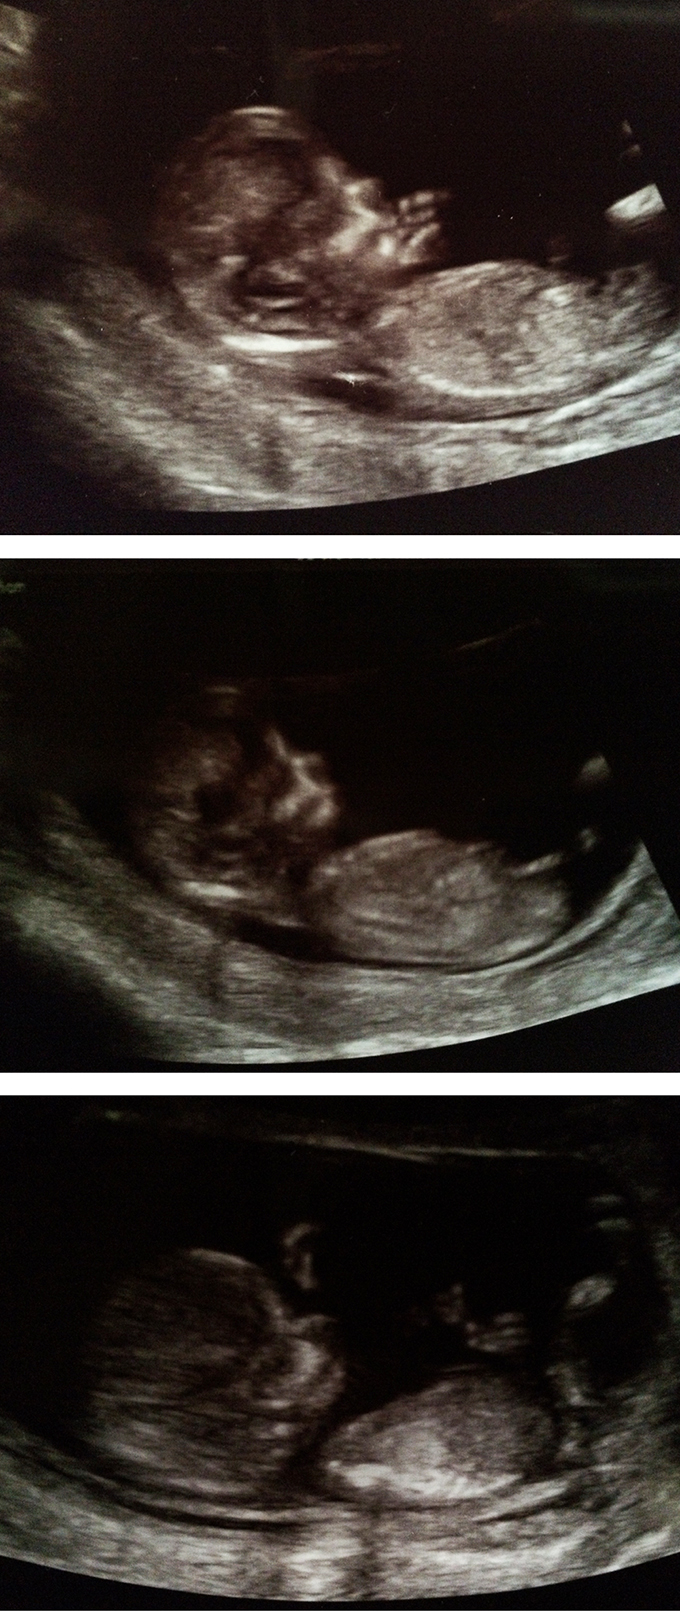

My 12wk 4d pics - any guesses?

Here are my ultrasound pics. The baby measured 12wk 4days, so I'm not sure if it's still too early to say anything. I would love to have a video for you to show, but I only got some pics. I saw a clear fork several times, but it was difficult for me to see the angle because the baby was moving all the time and looked curled. I saw this kind of fork (these are not from my pics):

Unfortunately I didn't get any pics to take home where "the fork" was showing, and I'm not sure if any of these are actually nub pictures. I can't tell... I don't know if what you see on pic 2 is a nub, because to me it starts quite high. But it is angled if it's a nub. I still get a feeling it's a boy, because I can't see any girl signs either. Can you?